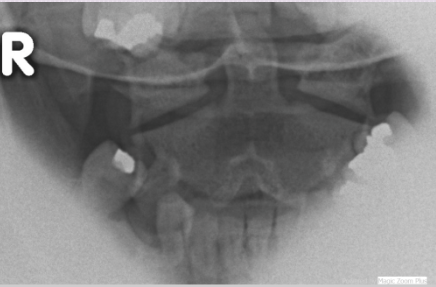

What type of radiograph and view is this?

Open Mouth Radiograph of (C1/C2)

What is this radiograph revealing?

Jefferson Burst Fracture (C1)

Open mouth radiograph